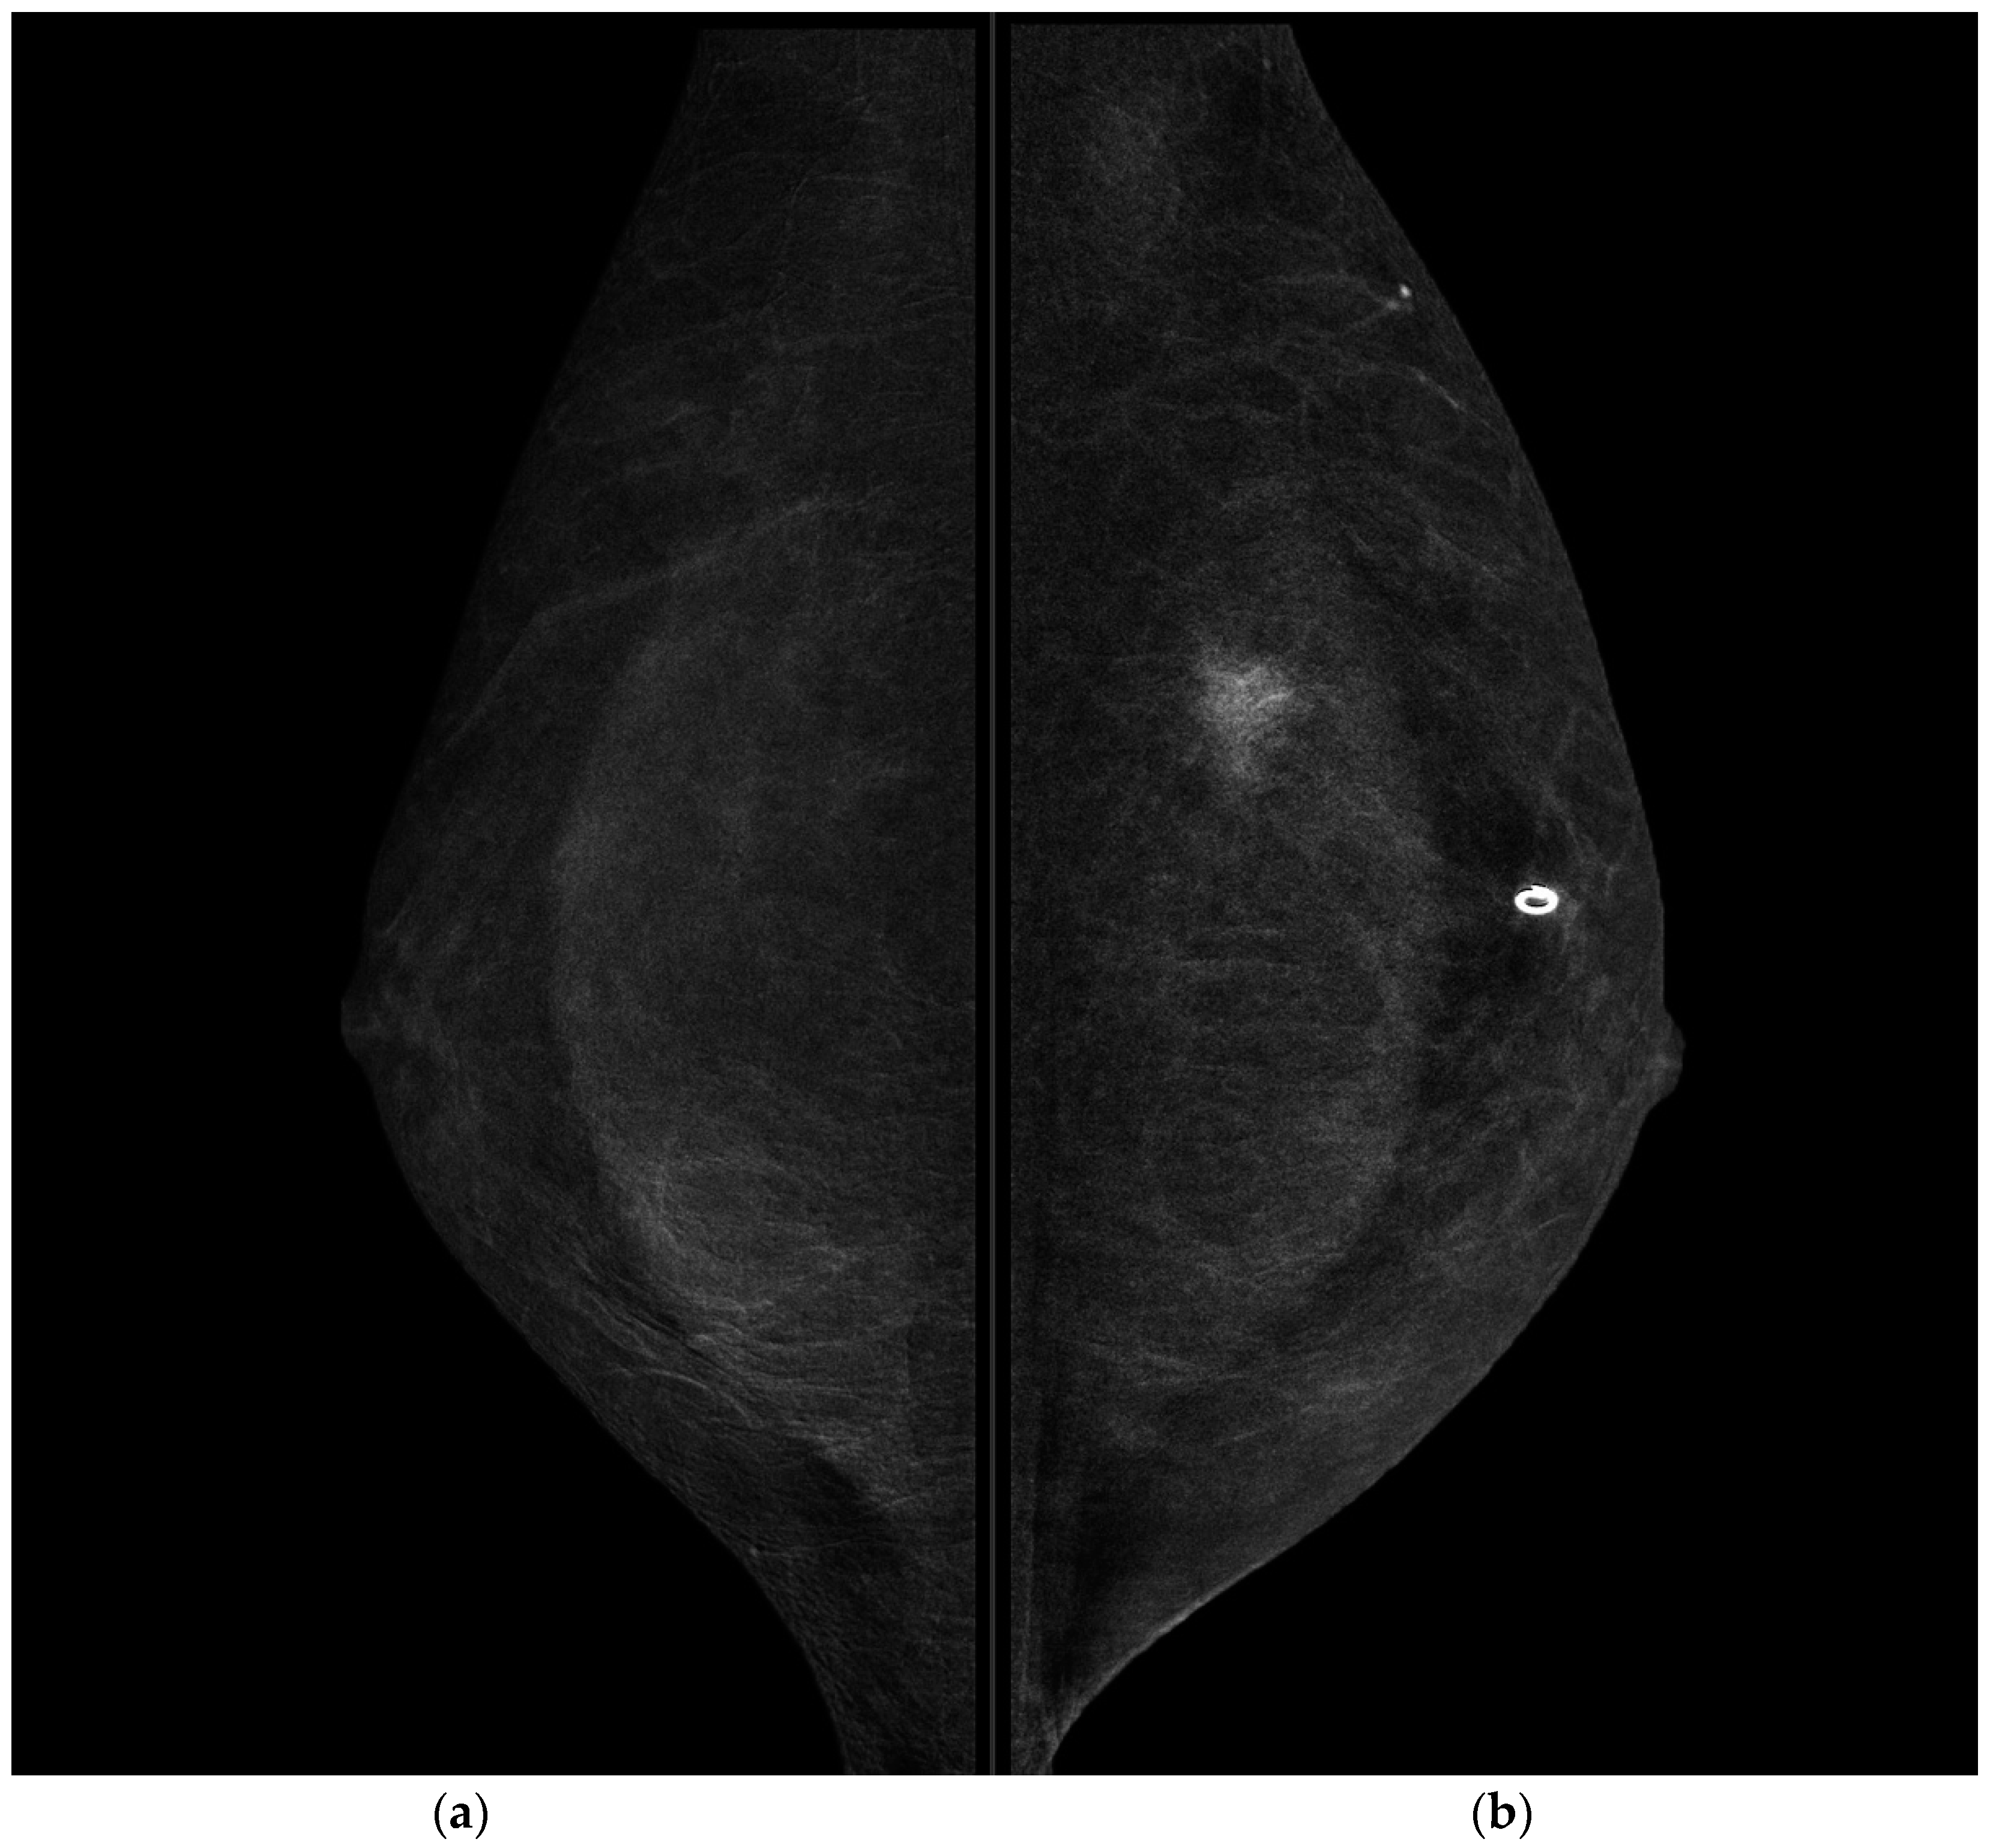

CESM showed the presence of a highly suspicious enhancement area with indistinct margins of 15 mm in the superior pre-pectoral region of the left breast, corresponding to the MR-detected lesion.

CESM also confirmed the presence of a metallic marker in the left retro-areolar breast, previously released in the breast biopsy site (Figure 1, Figure 2, Figure 3 and Figure 4).

Figure 2. CESM CC projections of the right breast (a) and left breast (b). Highly suspicious enhancement area with indistinct margins of 15 mm was detected in the pre-pectoral region of the left breast.